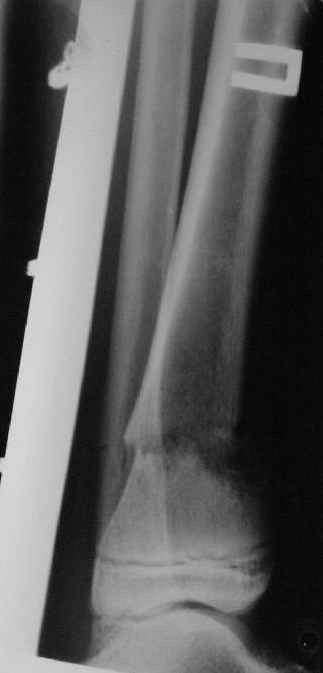

A>> Перелом костей н\3 правой голени со смещением.

AVM> Это от 13.10.04? А это близкие к первичным снимки?

Есть даже тень периостальной костной мозоли и сросшийся перелом

малоберцовой кости.

AVM> а был у больного перелом дистального метафиза большеберцовой с чисто

AVM> варусным смещением на фоне пластической деформации малоберцовой на том

AVM> же уровне и того же характера.

Это сросшийся перелом малоберцовой кости. И ложный сустав

н\3 б\берцовой кости.

Первичные